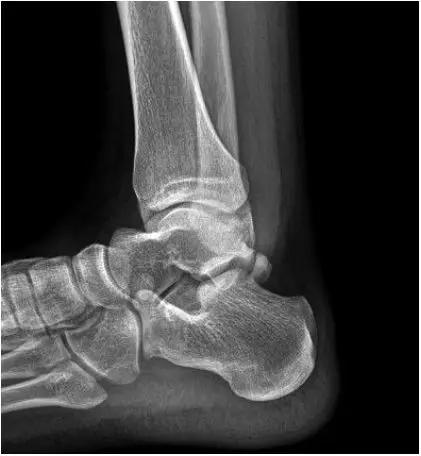

- 又称足球踝,通常为骨性撞击,由于经常性背屈导致胫骨远端关节面前缘与距骨颈部上缘骨赘反复撞击,有时滑膜软骨瘤病的游离体聚积在关节囊前部也会导致前撞击综合症。

- 放射学表现主要为胫骨前下缘与距骨颈部前上缘鸟嘴样骨刺形成。

放射学表现主要为胫骨前下缘与距骨颈部前上缘鸟嘴样骨刺形成

- Ⅰ度:滑膜撞击,X线片显示有炎性反应,骨刺大小为3mm;

- Ⅱ度:骨软骨反应性骨赘>3mm;

- Ⅲ度:严重的外生骨赘,可伴有或不伴有碎裂, 在距骨背侧可见继发性骨赘,常伴有骨赘的碎裂;

- Ⅳ度:距骨和胫骨关节骨性关节炎改变。